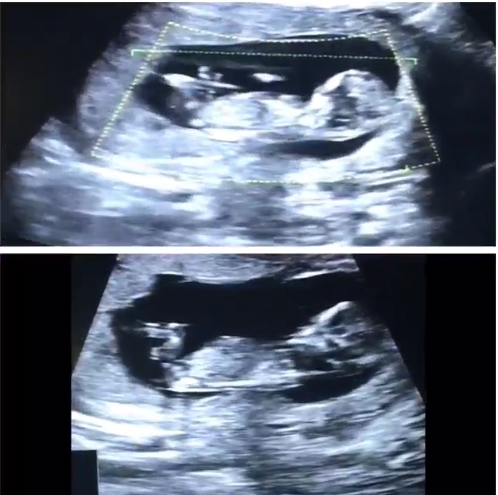

นักแสดงสาวสุดเซ็กซี่ กระแต ศุภักษร มีข่าวดีให้แฟนคลับได้เฮลั่นกันแล้ว โดยเมื่อวันที่ 4 พฤศจิกายน 2558 เจ้าตัวได้โพสต์ภาพอัลตราซาวด์ลูกลงในอินสตาแกรม พร้อมบอกว่า วันนี้ที่รอคอย ครั้งแรกที่ได้เจอเด็กน้อย #12w 3d แล้วนะคะ ขอฝากเนื้อฝากตัวกับพี่ ๆ น้อง ๆ ป้า ๆ น้า อาทุกท่านด้วยค่ะ